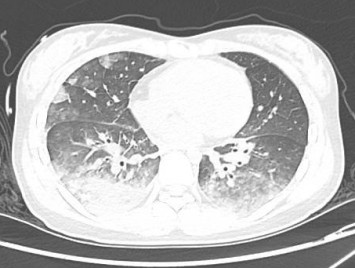

1 资料与方法患者女性,19岁,因“突发胸痛14 h”入院。患者14 h前无明显诱因出现胸骨后疼痛,呈紧缩感,伴有胸闷、呼吸困难,间断咳嗽。近期有听力下降、腹泻病史。8 h前就诊于外院时查体:体温测不出,Bp 53/36 mmHg(1 mmHg=0.133 kPa),呼吸40次/min, 脉搏137次/min,SPO2 93%,神志淡漠,全身皮肤湿冷,黏膜无黄染及出血点,颈静脉无怒张。听诊双肺呼吸音粗,可闻及满肺湿啰音,心音不清,腹部查体无异常,双下肢足背动脉搏动对称。化验结果提示WBC 29.3×109/L,NE 85.4%,TnT 93 ng/L,pro-BNP 2 047 pg/mL,PCT 0.11 ng/mL, 血气分析:pH 7.349,PCO2 31.2mmHg,PO2 67.2 mmHg,HCO3- 17.2 mmol/L,Lac 5.7 mmol/L。心电图提示:窦性心动过速、AVR导联ST段抬高,余导联ST段压低;床旁心脏超声提示EF 52%,二尖瓣中度返流、三尖瓣中重度返流,未见室壁节段性运动性异常。考虑心源性休克,原因尚不明确,给予机械通气、血管活性药物、补液等抗休克治疗,同时联系本院急诊ECMO团队,本院急诊ECMO团队到达现场后,患者突然出现室颤,给予胸外按压及电除颤后逐渐恢复窦律,立即进行V-A ECMO上机指征及预后评分SAVE评分评估,符合V-A ECMO上机适应证,约30 min成功上机运转,流量3.5 L/min,复查外周动脉血气分析: pH 7.305,PCO2 21 mmHg,PO2 73.4 mmHg,HCO3- 10.5 mmol/L,Lac 8.4 mmol/L。后转运至本院急诊病房,转运途中行生命体征、血气分析、ACT等常规监测,至病房后患者ECMO支持下血压仍需大剂量血管活性药物维持且脉压差较小,观察ECMO动静脉管路颜色极为接近,床旁经胸心脏超声提示主动脉瓣重度返流,为明确原因立即行急诊CT检查及床旁经食道超声心动图检查。本院肺CT(图 1)提示肺水肿,床旁经胸心脏超声提示主动脉瓣大量返流但心室收缩可,请超声影像科进一步行床旁经食道超声检查提示无冠窦呈瘤样凸向右房侧,瘤壁上可见宽约0.6 cm破口;主动脉瓣舒张期无冠瓣脱向左室流出道侧(图 2、图 3)。立即请心血管外科会诊,急诊行主动脉瓣机械瓣膜置换术+主动脉窦修补术+房间隔造口术+主动脉球囊反搏置入术+心脏起搏器置入术,术中探查与经食道超声所见相符(图 4、图 5),考虑左心功能差,左心压力较高,行房间隔造口术。术后复查胸片肺水肿基本消失(图 6),继续呼吸机与ECMO支持,因患者肺功能良好,自主呼吸良好,为减少呼吸机相关肺损伤、呼吸机相关肺炎等发生,术后第4天神志清醒后拔除气管插管,机械通气减轻左心前后负荷的作用去除后,继续ECMO与IABP支持,ECMO增加左心后负荷时IABP可降低左室后负荷,达到左心减压的目的,术后第10天心功能恢复,下调ECMO流量后循环可维持,予以撤离ECMO,术后第12天撤离IABP,后停用肝素持续泵入抗凝,达肝素皮下注射联用华法林口服抗凝3 d后,单用华法林口服抗凝,维持INR达标,在康复期间患者活动时左下肢疼痛,左侧足背动脉搏动减弱,下肢动静脉超声提示左侧股浅动脉血栓形成,期间增加华法林剂量后血栓未见明显变化,后行下肢股浅动脉切开取栓术,术后33 d患者完全康复顺利出院。

| 图 1 术前肺CT |

主动脉窦瘤较小或未破裂时患者可能完全没有症状,破裂后根据破口大小、破入部位的不同会产生不同的血流动力学变化,产生相应的临床表现也会不同。当破入右心时,主动脉与右心之间的压力差增大,引起右心容量负荷增加,严重者可出现肺动脉高压;与此同时,因大量左向右分流导致体循环血流量明显减少,易进展为急性心源性休克[6-8]。本案例患者术中探查考虑为先天性无冠窦瘤,既往窦瘤未破裂时无明显症状,破裂后患者突发胸痛、胸闷、呼吸困难,很快出现心源性休克,且V-A ECMO支持下患者血压仍需大剂量血管活性药物维持且脉压差较小,与窦瘤破入右房后体循环血流量明显减少出现的血流动力学改变相符,右心容量负荷增加导致的肺水肿与肺CT表现一致。